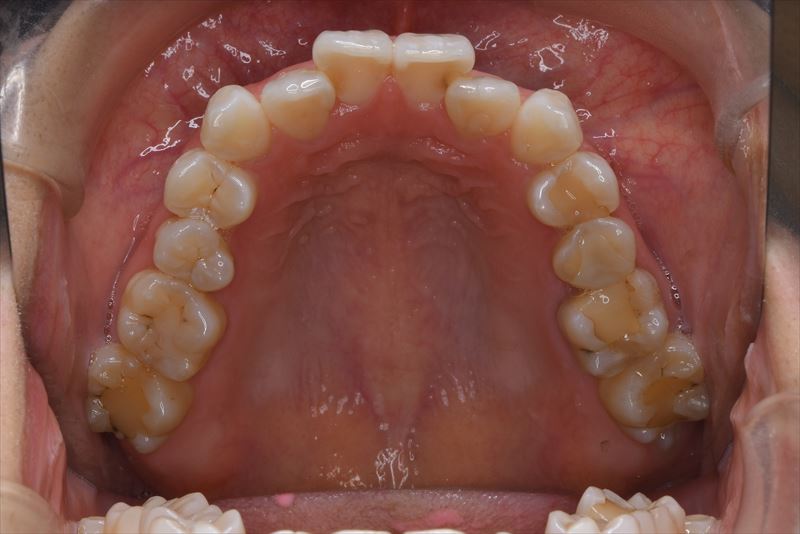

治療前

- 両側2番クロスバイト、叢生、上顎左側6番根尖病巣

- 上顎左側6番は失活歯で根尖病巣を認めたため抜歯し、上顎左側8番を代わりに使用することとしました。アンカースクリューを使用することにより、健康な歯を抜歯せず臼歯の遠心移動で叢生の改善できました。治療期間が短かく良好な咬合を獲得できました。